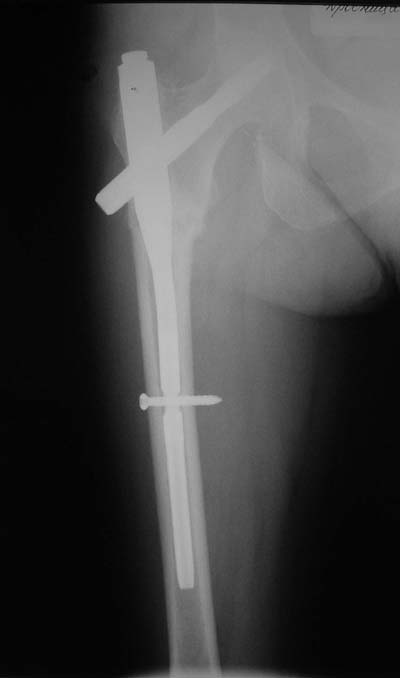

Да? Качество рентгенограмм конечно неочень, но ведь это нестабильный перелом 31.А2.2, не так ли?

Не думаю так. см вложение.

> Не думаю так. см вложение.